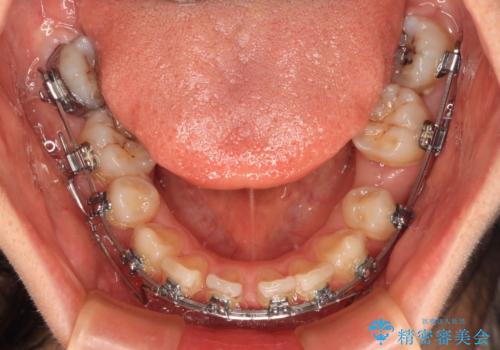

- メタルブラケット

上下臼歯の咬み合わせ改善には補助装置を、深い咬み合わせ改善にはユーティリティーアーチを活用し、ワイヤー装置にて矯正治療を行うこととしました。

甚大な咬合力に抵抗して過蓋咬合を改善する必要があり、更には口元が引っ込みすぎることがないように仕上げていく必要もあったため、治療期間は3年を超えましたが、当初計画通りの仕上がりで治療を終えることができました。